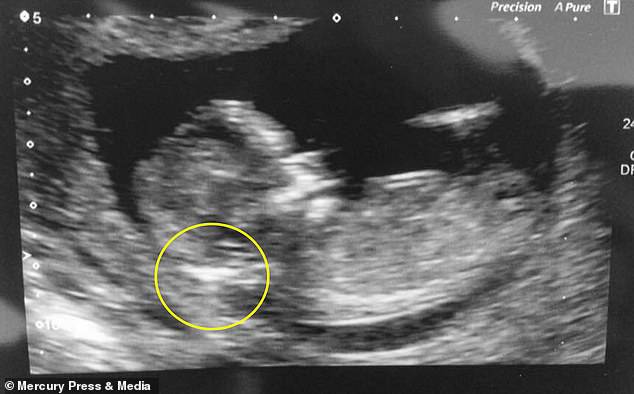

“Quando ero all’ecografia per la 12° settimana di gravidanza, ho capito subito che c’era qualcosa che non andava. L’ostetrica sembrava preoccupata. Ci ha chiesto se potevamo andare nella stanza accanto e parlare”.

La ventiduenne Jordan ha riferito che i medici hanno detto loro che c’era un’alta probabilità che il bimbo avesse la Sindrome di Down a causa dell’elevato fluido sul collo.

“Noi eravamo sconvolti, perché i medici ci hanno detto che aveva la Sindrome di Down e l’ecografia sembrava dimostrarlo”.